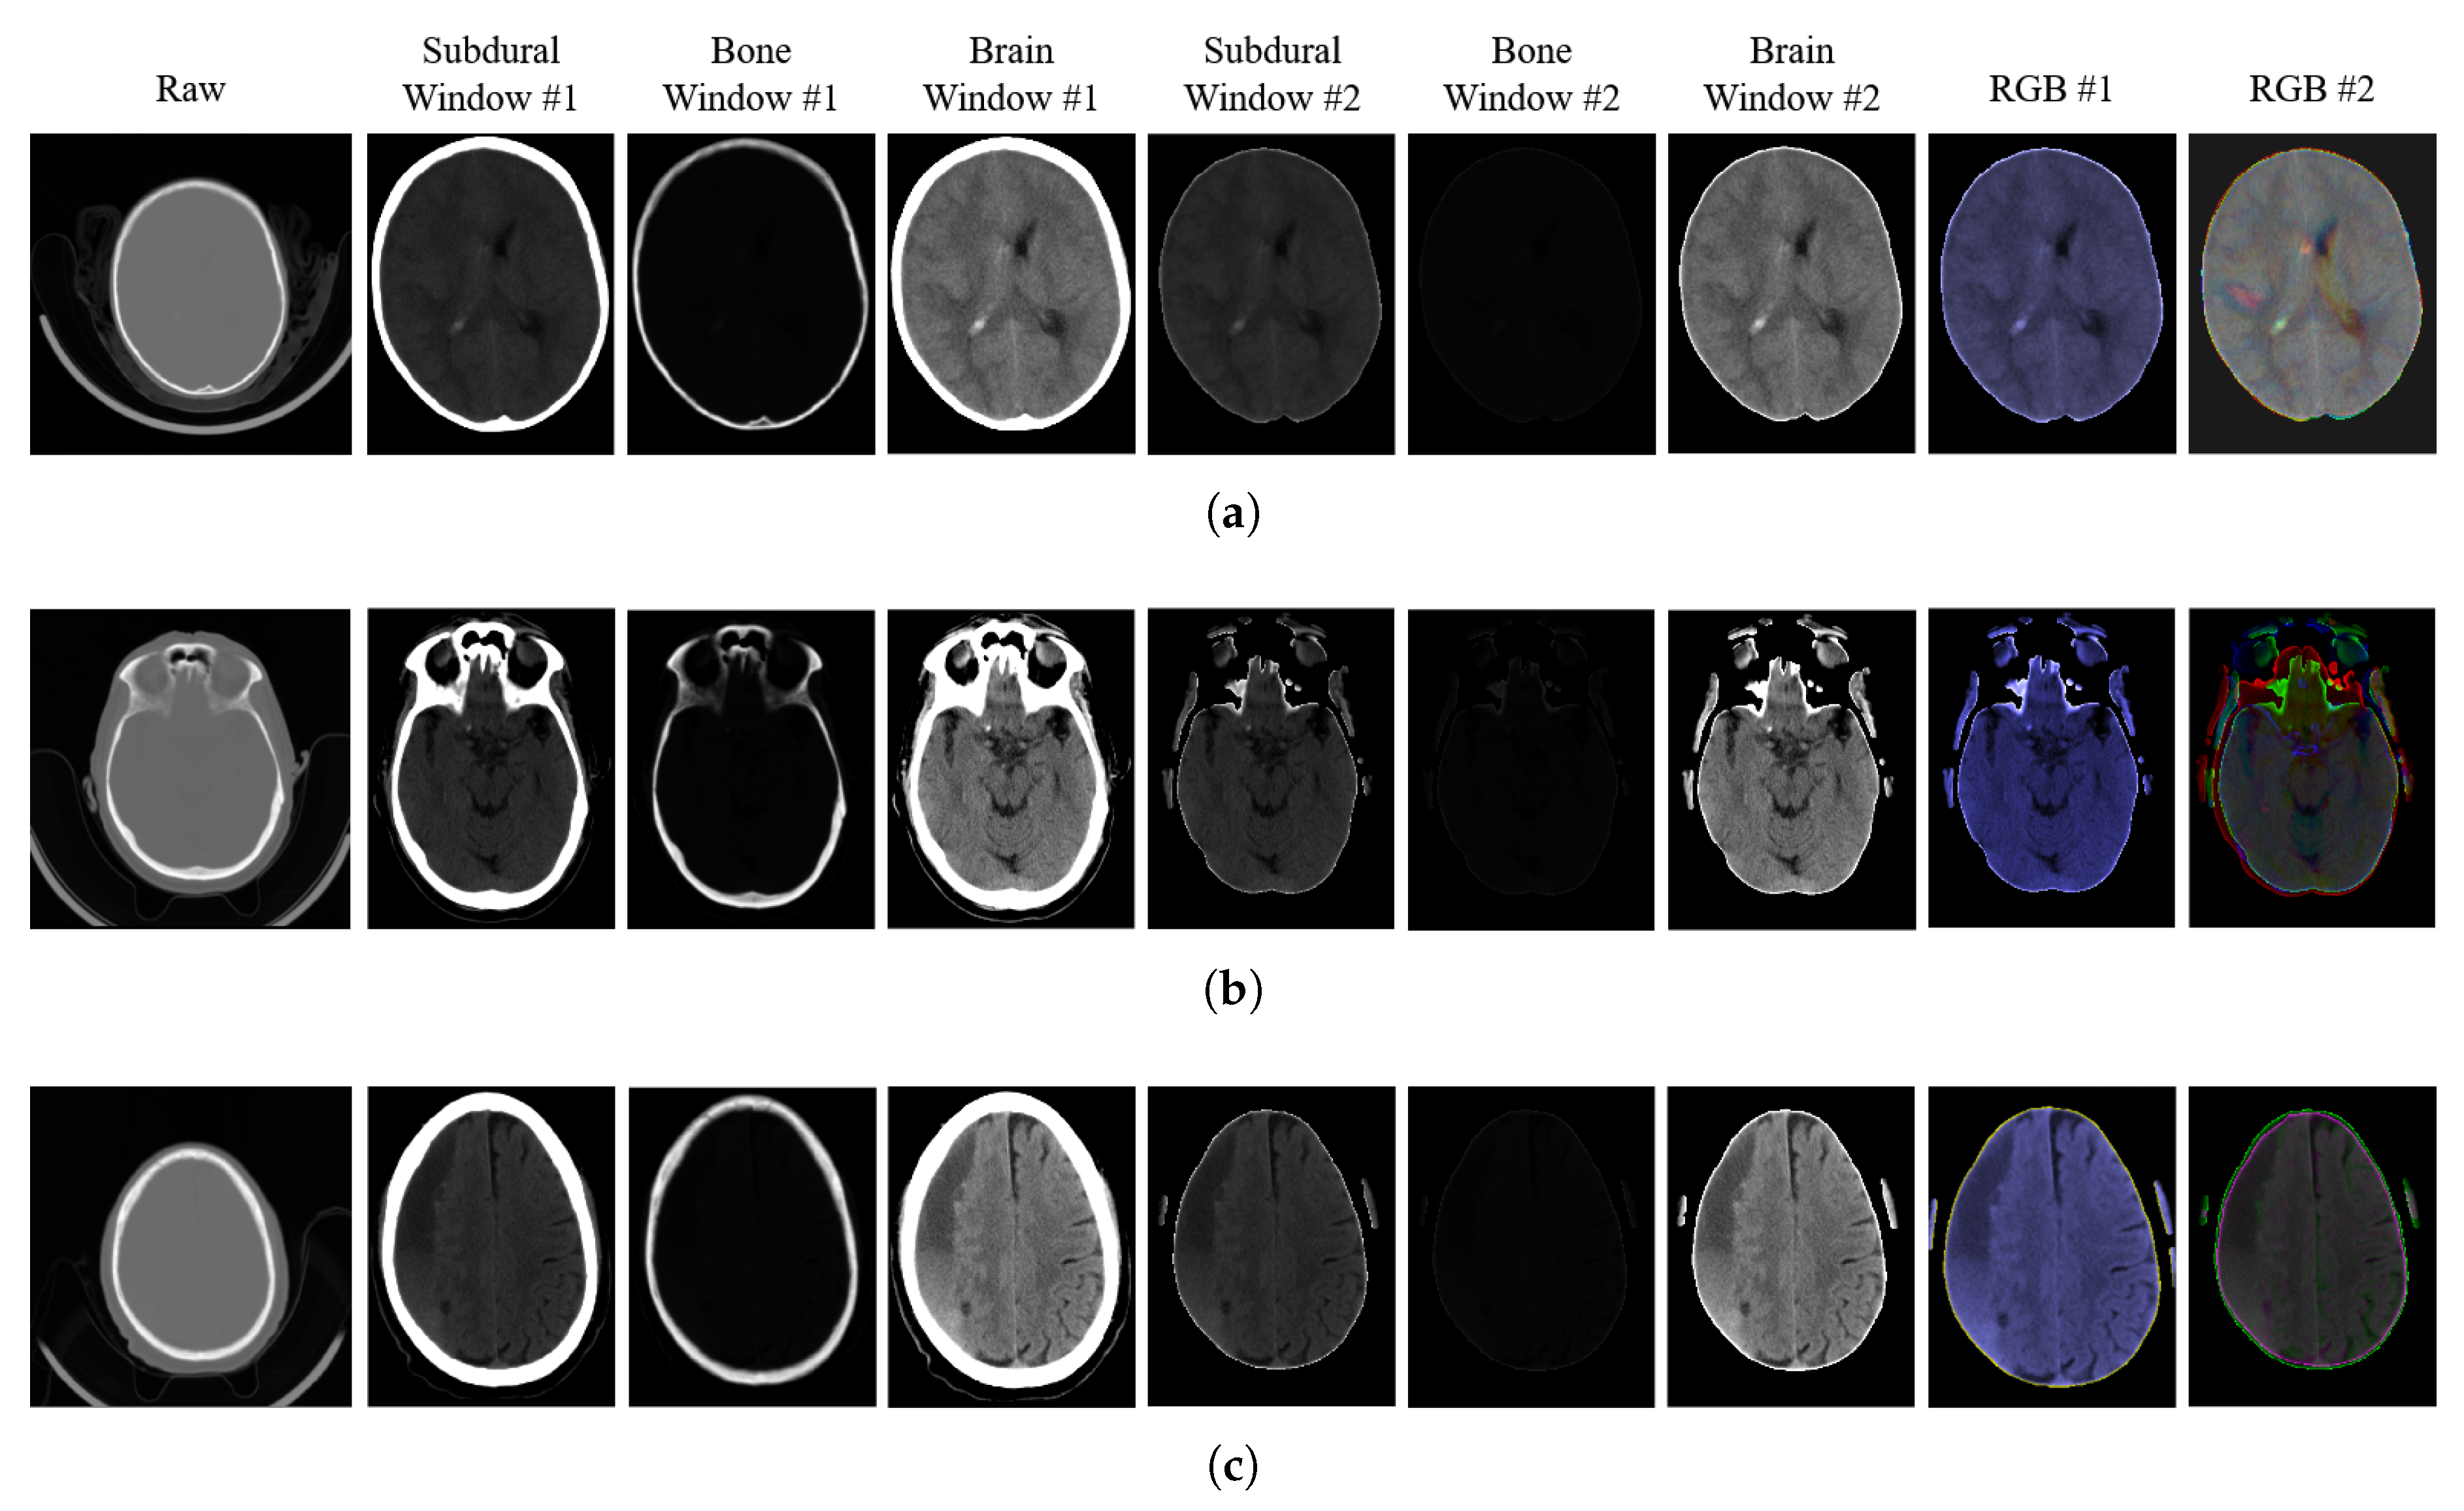

The data preprocessing starts with applying dedicated intensity windows to the CT image, followed by the skull removal algorithm. We use three intensity windows (in Hounsfield units—HU): L = 100, W = 200 (subdural window), L = 600, W = 2800 (bone window), and L = 40, W = 80 (brain window). Images after the intensity windowing are normalized to the 0–1 range. Then, we determine the region of interest (ROI) embracing the cranial area as a bounding box framing the largest binary object in the subdural image after binarization using the Otsu method [26]. The skull removal process is performed on the subdural-window image by extracting pixels with the highest intensities corresponding to the bone regions and replacing them with zero-valued pixels. Due to soft tissue outside the skull, the morphological opening is applied to extract the intracranial area.

After the skull removal, the data preparation splits into two branches related to the architecture of the following CNNs. In either branch, preprocessing concludes with preparing RGB images for the feature extraction part of the CNNs. In the left branch in Figure 2, the 3D image structure is composed of three windowed slices with skull pixels replaced with zeros. The right branch employs spatial information by combining three subsequent CT slices from the current scan, all in the subdural window and with a removed skull. The i-th slice under consideration is put into the green (G) channel, while the red (R) and blue (B) channels contain slices preceding and following the i-th one, respectively. Figure 3 shows the results of subsequent preprocessing stages for three sample CT slices.

Figure 3.

Illustration of the results of subsequent preprocessing stages in three sample CT slices (a–c). Columns (left to right): raw CT slice before region of interest (ROI) extraction, subdural-window image, brain-window image, bone-window image (first three before and next three after skull removal), a stack of three CT-windowed images (Branch #1), a stack of three neighboring slices (Branch #2).